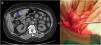

Tras antibioterapia empírica y drenaje percutáneo, existe persistencia de la lesión, por lo que se decide intervención quirúrgica urgente: mediante laparotomía subcostal, se realiza drenaje quirúrgico en dos ocasiones con una semana de intervalo entre ambas intervenciones, sin mejoría clínica ni radiológica, y sin hallar la etiología del absceso. Al séptimo día postoperatorio es alta con seguimiento ambulatorio permaneciendo asintomática y afebril. En la TAC de control, se visualiza nuevamente la lesión acompañada de una imagen lineal de densidad ósea de 3cm en relación con el antro gástrico y en íntimo contacto con el absceso (fig. 1a) no claramente visualizada en las pruebas de imagen previas.

a) Corte axial de la TAC, donde se objetiva cuerpo extraño (espina de pescado, marcado con la flecha azul); y a la derecha, b) imagen intraoperatoria donde se observa la espina en el trayecto fistuloso hacia el hígado. Los colores de la figura solo pueden apreciarse en la versión electrónica del artículo.

Se programa intervención quirúrgica, relaparotomía y desbridamiento del plastrón inflamatorio que engloba antro gástrico, ángulo hepático del colon y segmentos V y VI hepáticos, con una espina de pescado de 4cm que perfora cara lateral de la curvatura menor gástrica introduciéndose en el hígado. Se realiza resección del trayecto fistuloso, y cierre del mismo, extracción del cuerpo extraño y resección hepática de la zona abscesificada (fig. 1b). Posteriormente fue alta al octavo día, y actualmente sin recurrencia de la enfermedad.